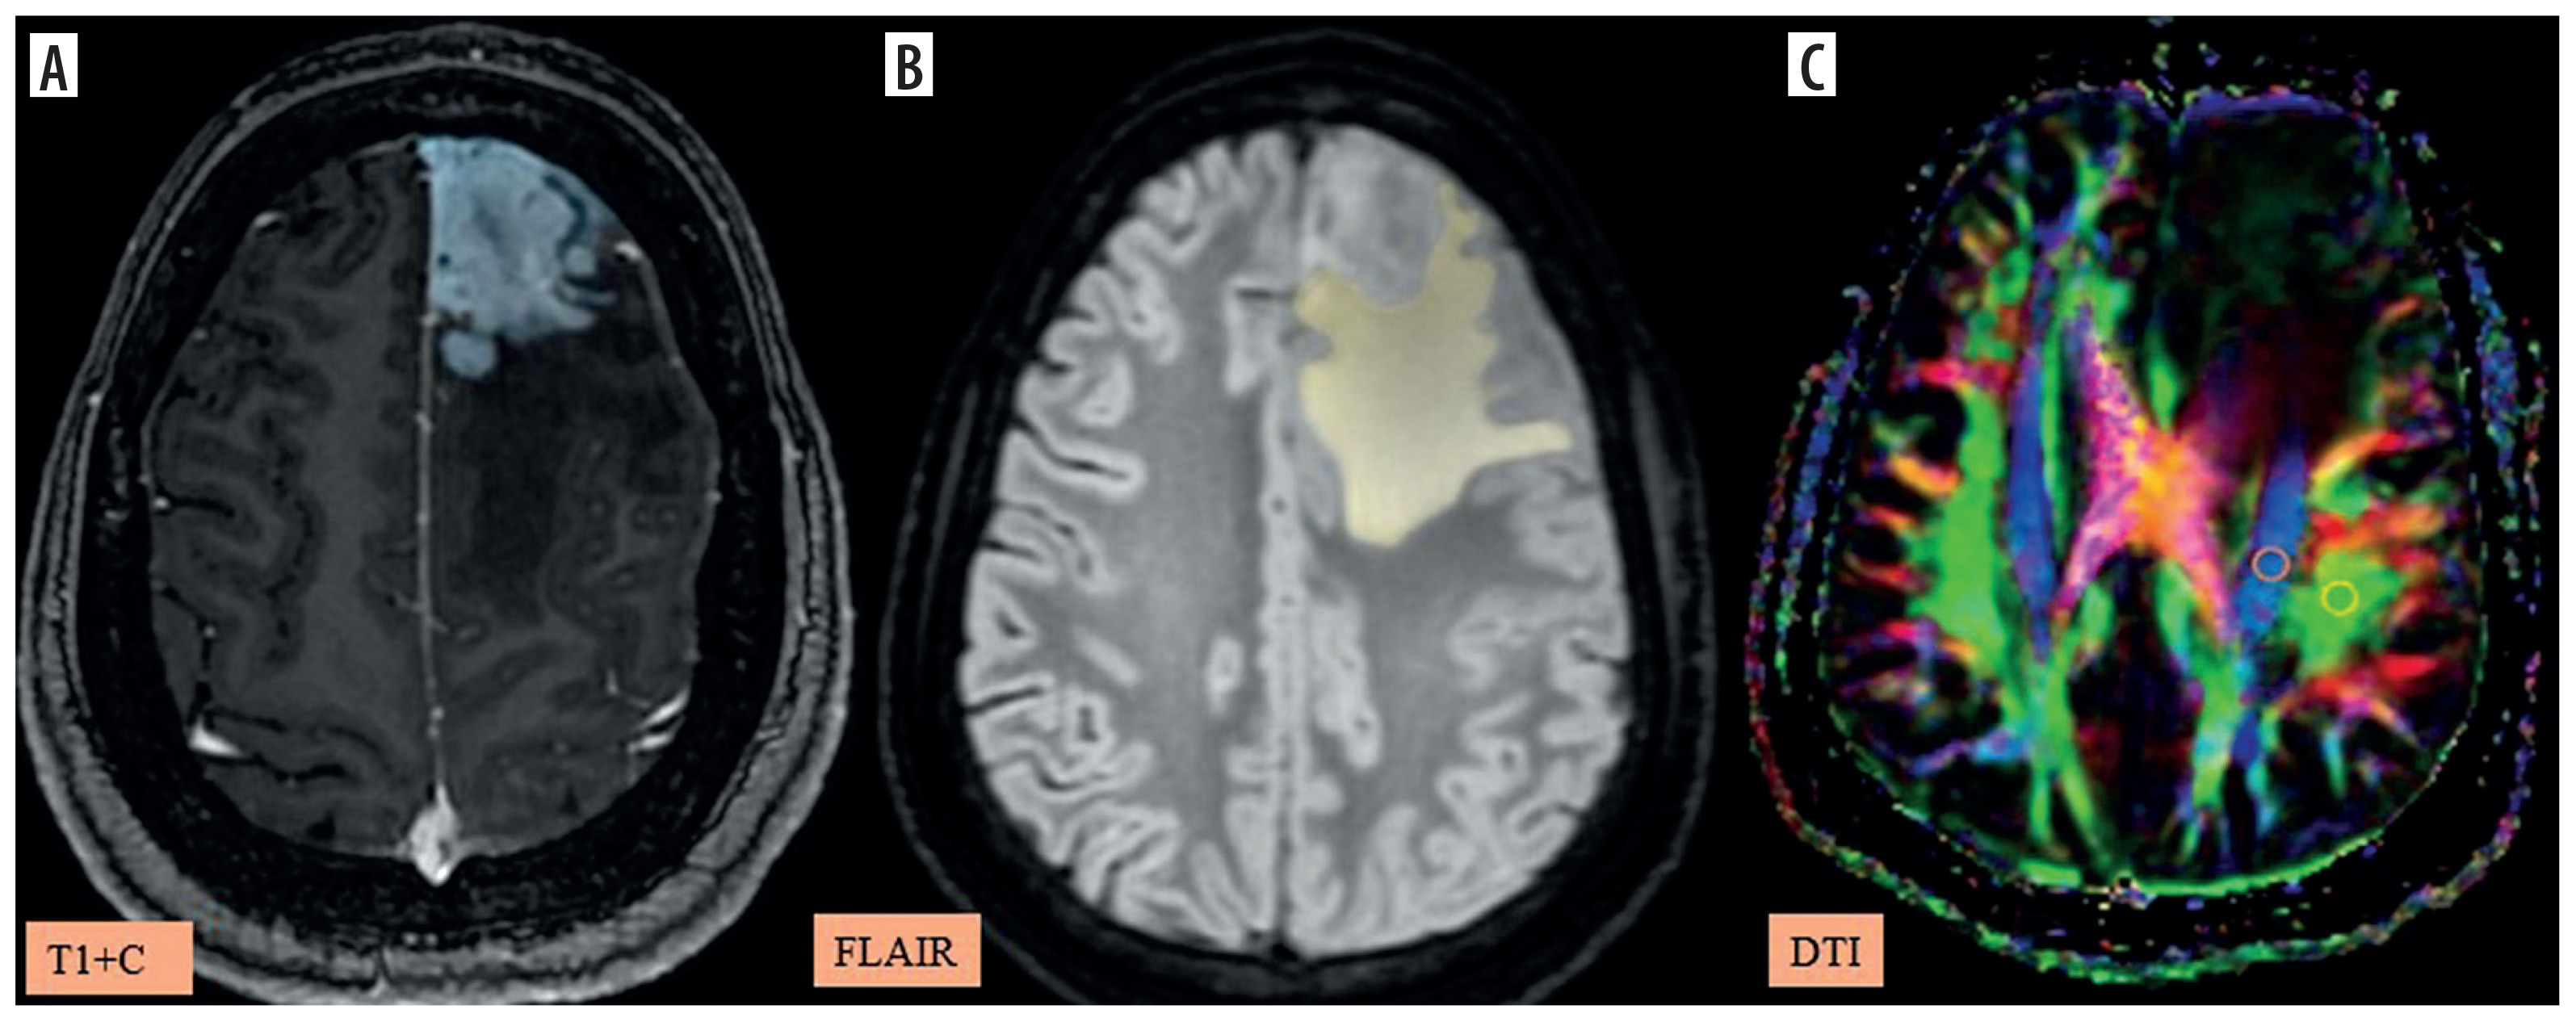

Figure 4

A-C) Patient with a low-grade glioma in the left frontal region presenting with headache and seizures. A) and B) Axial fluid-attenuated inversion recovery (FLAIR) images show the segmented peritumoral oedema (yellow) and tumour volume (blue). C) Image describing the calculation of the diffusion tensor image analysis along the perivascular space (DTI-ALPS) index using two regions of interest (ROIs) drawn within the projection (blue) and association (green) fibres in the left periventricular region